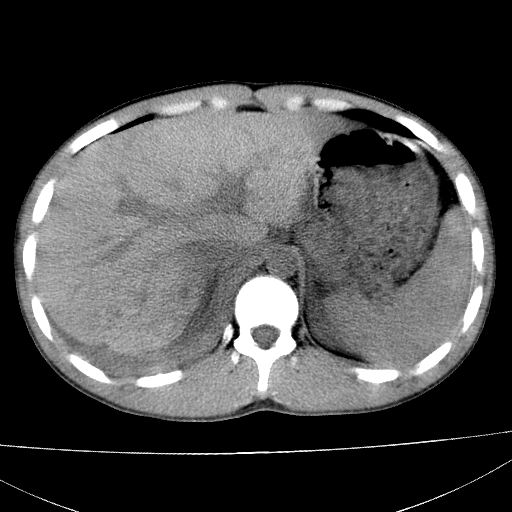

标题: CT15860:男,21岁,腹部外伤2小时伴胸疼。 [打印本页]

标题: CT15860:男,21岁,腹部外伤2小时伴胸疼。

b超示:肝破裂。

肝脏及肾脏明显有损伤性改变并激发腹腔内积液(血),以肝脏撕裂及肾周积血显著。

1)肝破裂伴腹腔积液(血)。2)右肾破裂伴右肾包膜下及肾周血肿。3)腹部空腔脏器穿孔可能。4)右侧少量胸腔积液(血)。

1)肝破裂伴腹腔积液(血)。2)右肾破裂伴右肾包膜下及肾周血肿。3)右侧少量胸腔积液(血)。

肝、右肾包膜下血肿,右侧腰大肌及腹膜后血肿;腹腔少量积血;腹腔疑有少量游离气体伴肠破裂。

1肝挫伤伴腹腔积液。2右肾挫裂伤伴右肾包膜及肾后间隙肿血肿。3右肾脏周围的积气,十二指肠显示结构不清,考虑十二指肠降部破裂可能性大。